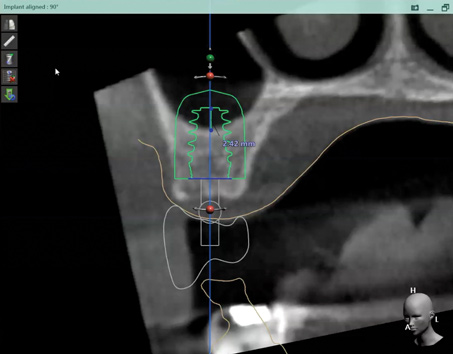

Fig 2. CBCT images: axial (Fig 2) and cross-sectional (Fig 3) views, and 3D reconstruction view (Fig 4) with virtually planned implant Nos. 8 and 9.

Figure 2

Fig 3. CBCT images: axial (Fig 2) and cross-sectional (Fig 3) views, and 3D reconstruction view (Fig 4) with virtually planned implant Nos. 8 and 9.

Figure 3

Fig 4. CBCT images: axial (Fig 2) and cross-sectional (Fig 3) views, and 3D reconstruction view (Fig 4) with virtually planned implant Nos. 8 and 9.

Figure 4